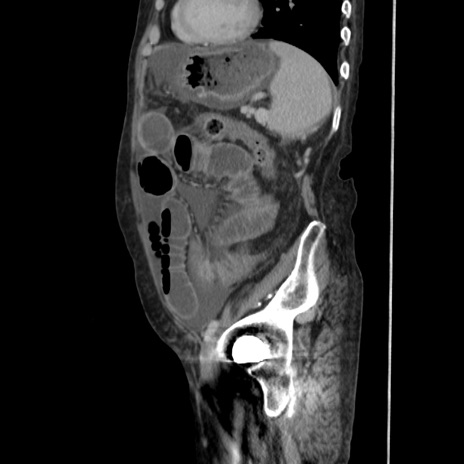

症例31(矢状断像)

【症例】80歳代 女性

【主訴】腹部膨満感

【現病歴】他院にて肝硬変にてフォロー中。1週間前から便秘、腹部膨満感、臍部腫瘤あり受診となる。

【既往歴】肝硬変

【身体所見】腹部膨隆あり、皮膚変化なし、疼痛なし。

【データ】WBC 4600、CRP 0.25